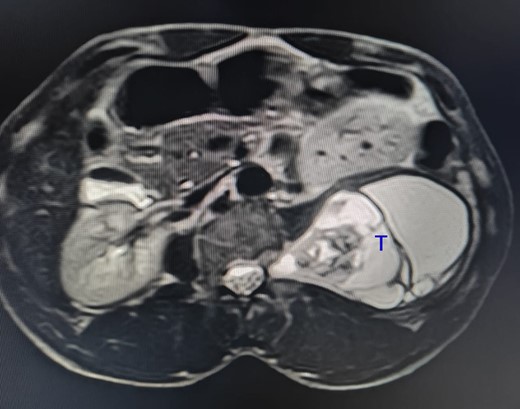

A man in his 30s presented with symptoms suggestive of irritable bowel symptoms with increased bowel movements coinciding with the onset of colicky abdominal pain for the past 8 months. The bowel movements relived his pain and had no remission from his symptoms. He had no relevant medical comorbidities in the past. The patient had normal vitals. There were no physical exam abnormalities except for a slight fullness in the left renal angle (Fig. 1). There was nothing significant on a rectal examination. An X-ray of the chest showed normal findings. Blood investigations showed: haemoglobin 130 g/l, total leukocyte: 7.4 × 109/l, serum creatinine 0.52 mg/dl, fasting blood sugar 90 g/dl, alanine transaminase 26 U/L, aspartate transaminase 42 U/L, alkaline phosphatase 32 U/L and total bilirubin 0.8 mg/dL. Ultrasonography showed a 10-cm mass, with mixed echogenicity. Posterior to the left kidney. Colonoscopy was normal. An abdominal CT scan showed a paravertebral tumour with peripheral enhancement and heterogenous contrast within the tumour (Fig. 2). The tumour showed high intensity on a T2-weighted MRI (Fig. 3). The left kidney and colon were displaced anteriorly. Fine-needle aspiration biopsy was inconclusive. The clinical diagnosis was a retroperitoneal schwannoma. On laparotomy, the left colic vessels appeared to be splayed by the tumour (Fig. 4). The tumour 11 × 6 × 3 cm3 (Fig. 5), which seems to be arising from the L2 nerve, was resected completely (Fig. 6). The patient had no sensory or motor loss postoperatively. He was discharged without complications on the 10th postoperative day. His colonic symptoms had disappeared after surgery. The gross appearance of the resected tumour showed cysts and haemorrhage patches (Fig. 7). Histopathology showed areas of hypercellularity (Antony A) and hypocellularity (Antony B) with degenerative changes leading to nuclear atypia and cystic spaces, typical of an ancient schwannoma (Figs 8–11). Immunohistochemistry with S-100 was positive (Fig. 12). He was devoid of digestive symptoms or radiological evidence of recurrence at 12 months.

The tumour (T) shows a high-intensity signal on a T2-weighted MRI.